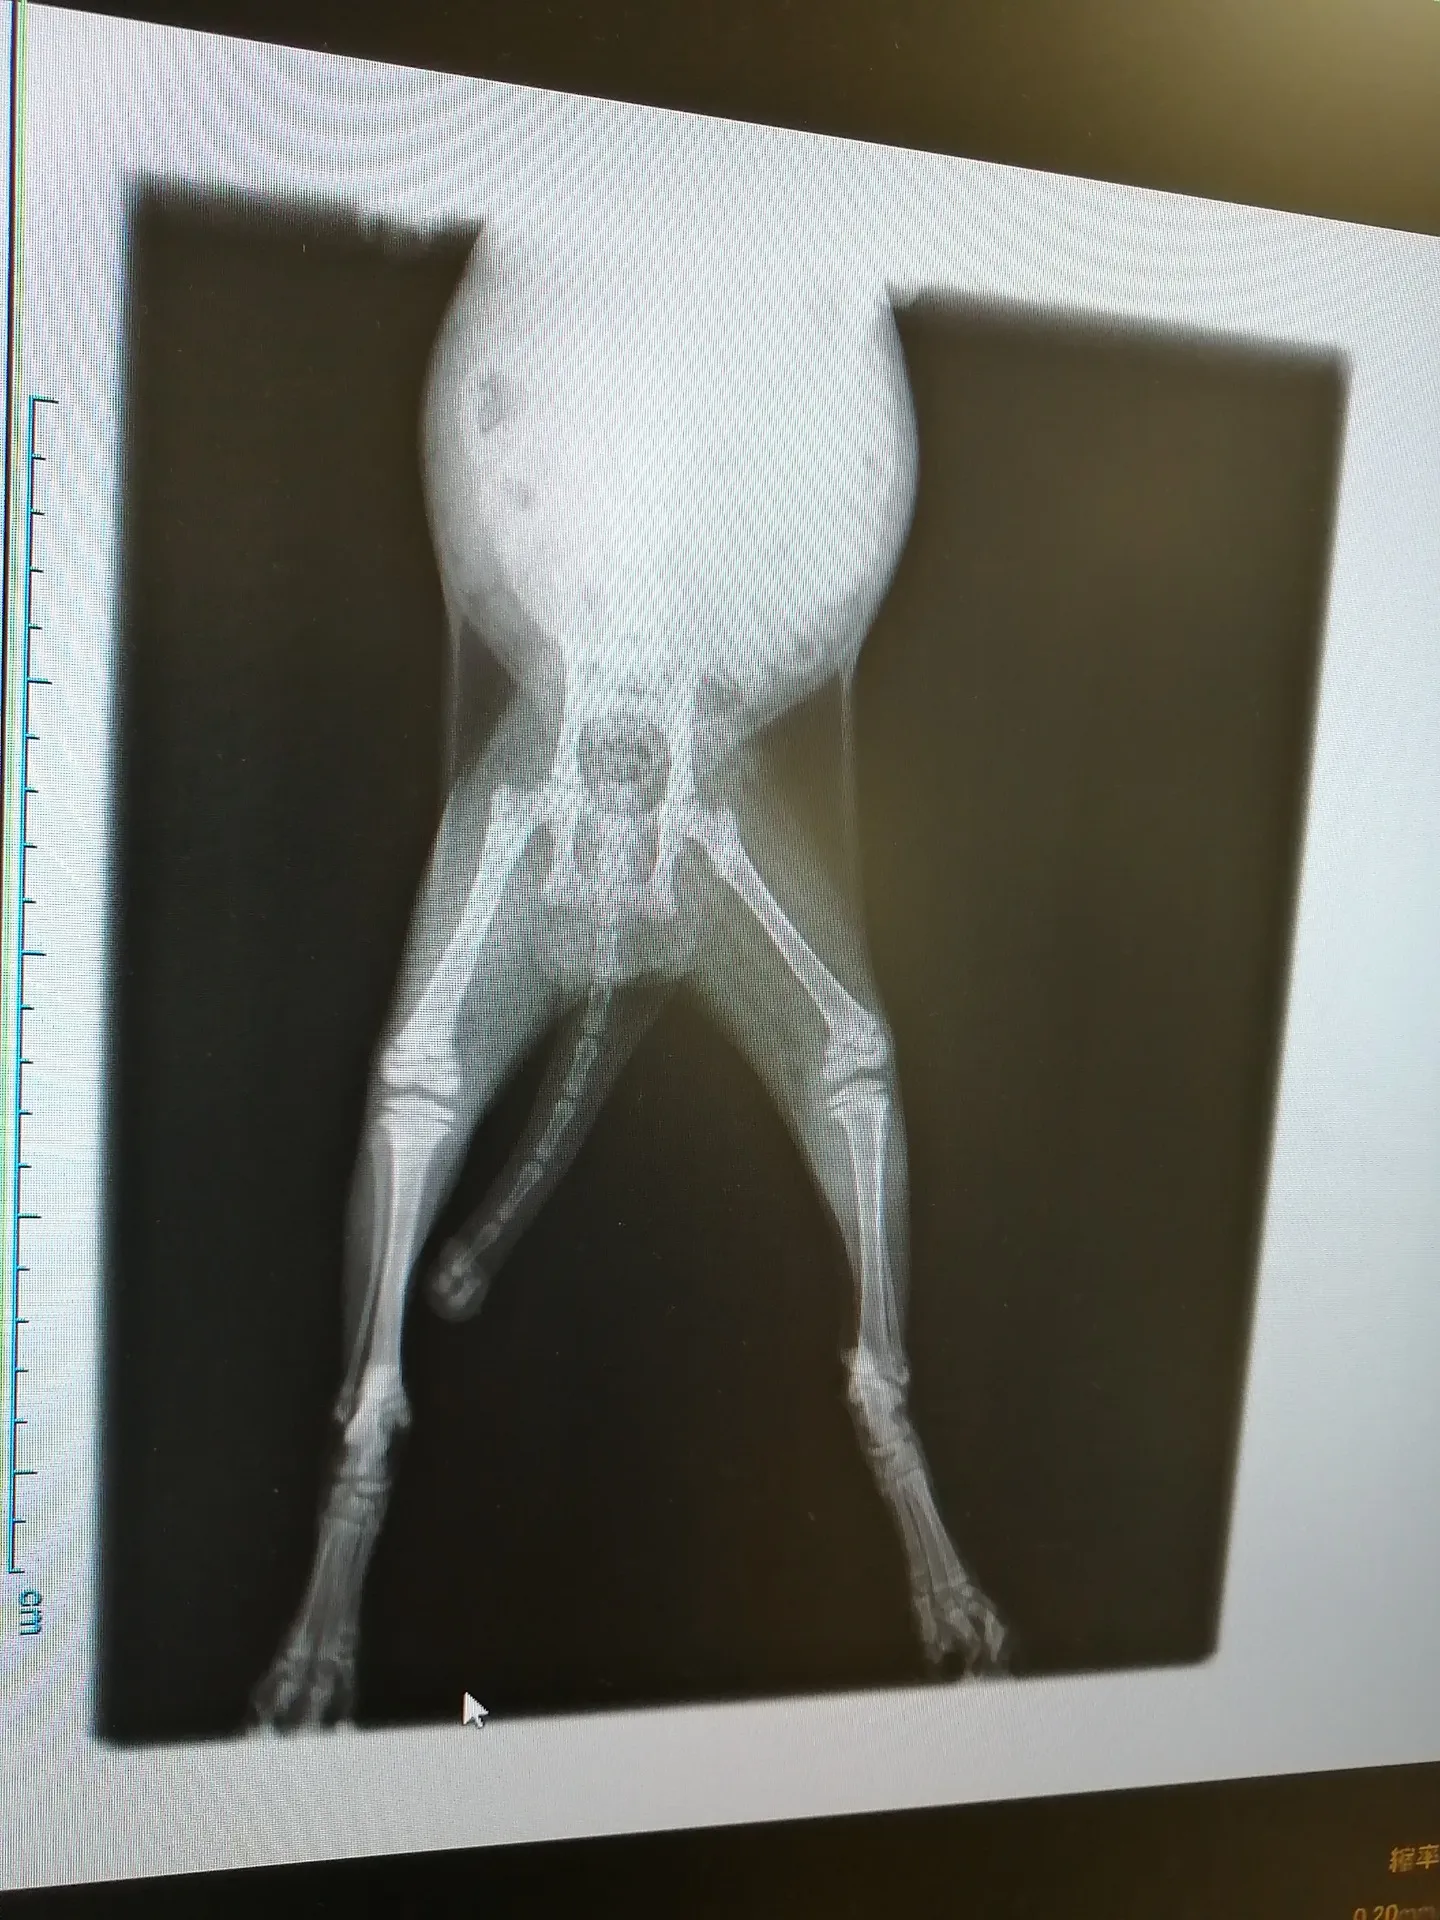

レントゲンの結果が出ました。

左後脚、骨と骨の間に隙間があり、開いていて右脚と比べると明らかな違いがあります。

歩き方がおかしいのはその隙間幅が原因でした。

では、何故そうなっているのか、異骨の原因は?

と尋ねる私に、現時点の資料と見解では確定できないけど、仔猫すぎるため特化した治療ができない事、急な治療が必要な状態ではない事が告げられ、サプリメントを服用しながら成長過程を見ていく事になりました。